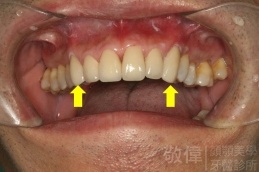

| 6 | 前牙美容 | 矯正+牙齦增補+晶鑽全瓷冠 | ||

| 7 | 前牙美容 | 矯正+晶鑽全瓷冠 | ||

| 8 | 前牙美容 | 快速矯正之美容晶瓷貼片及晶鑽瓷冠 | ||